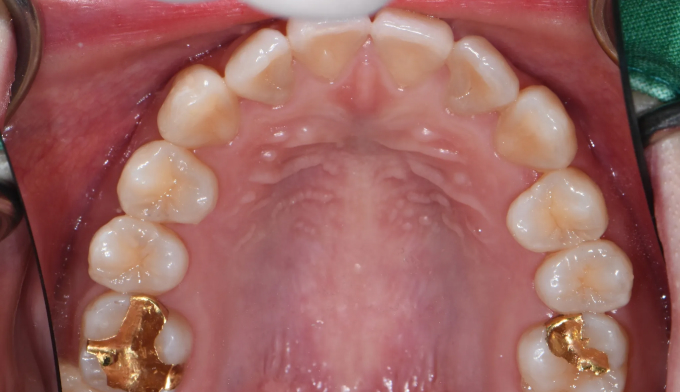

Before